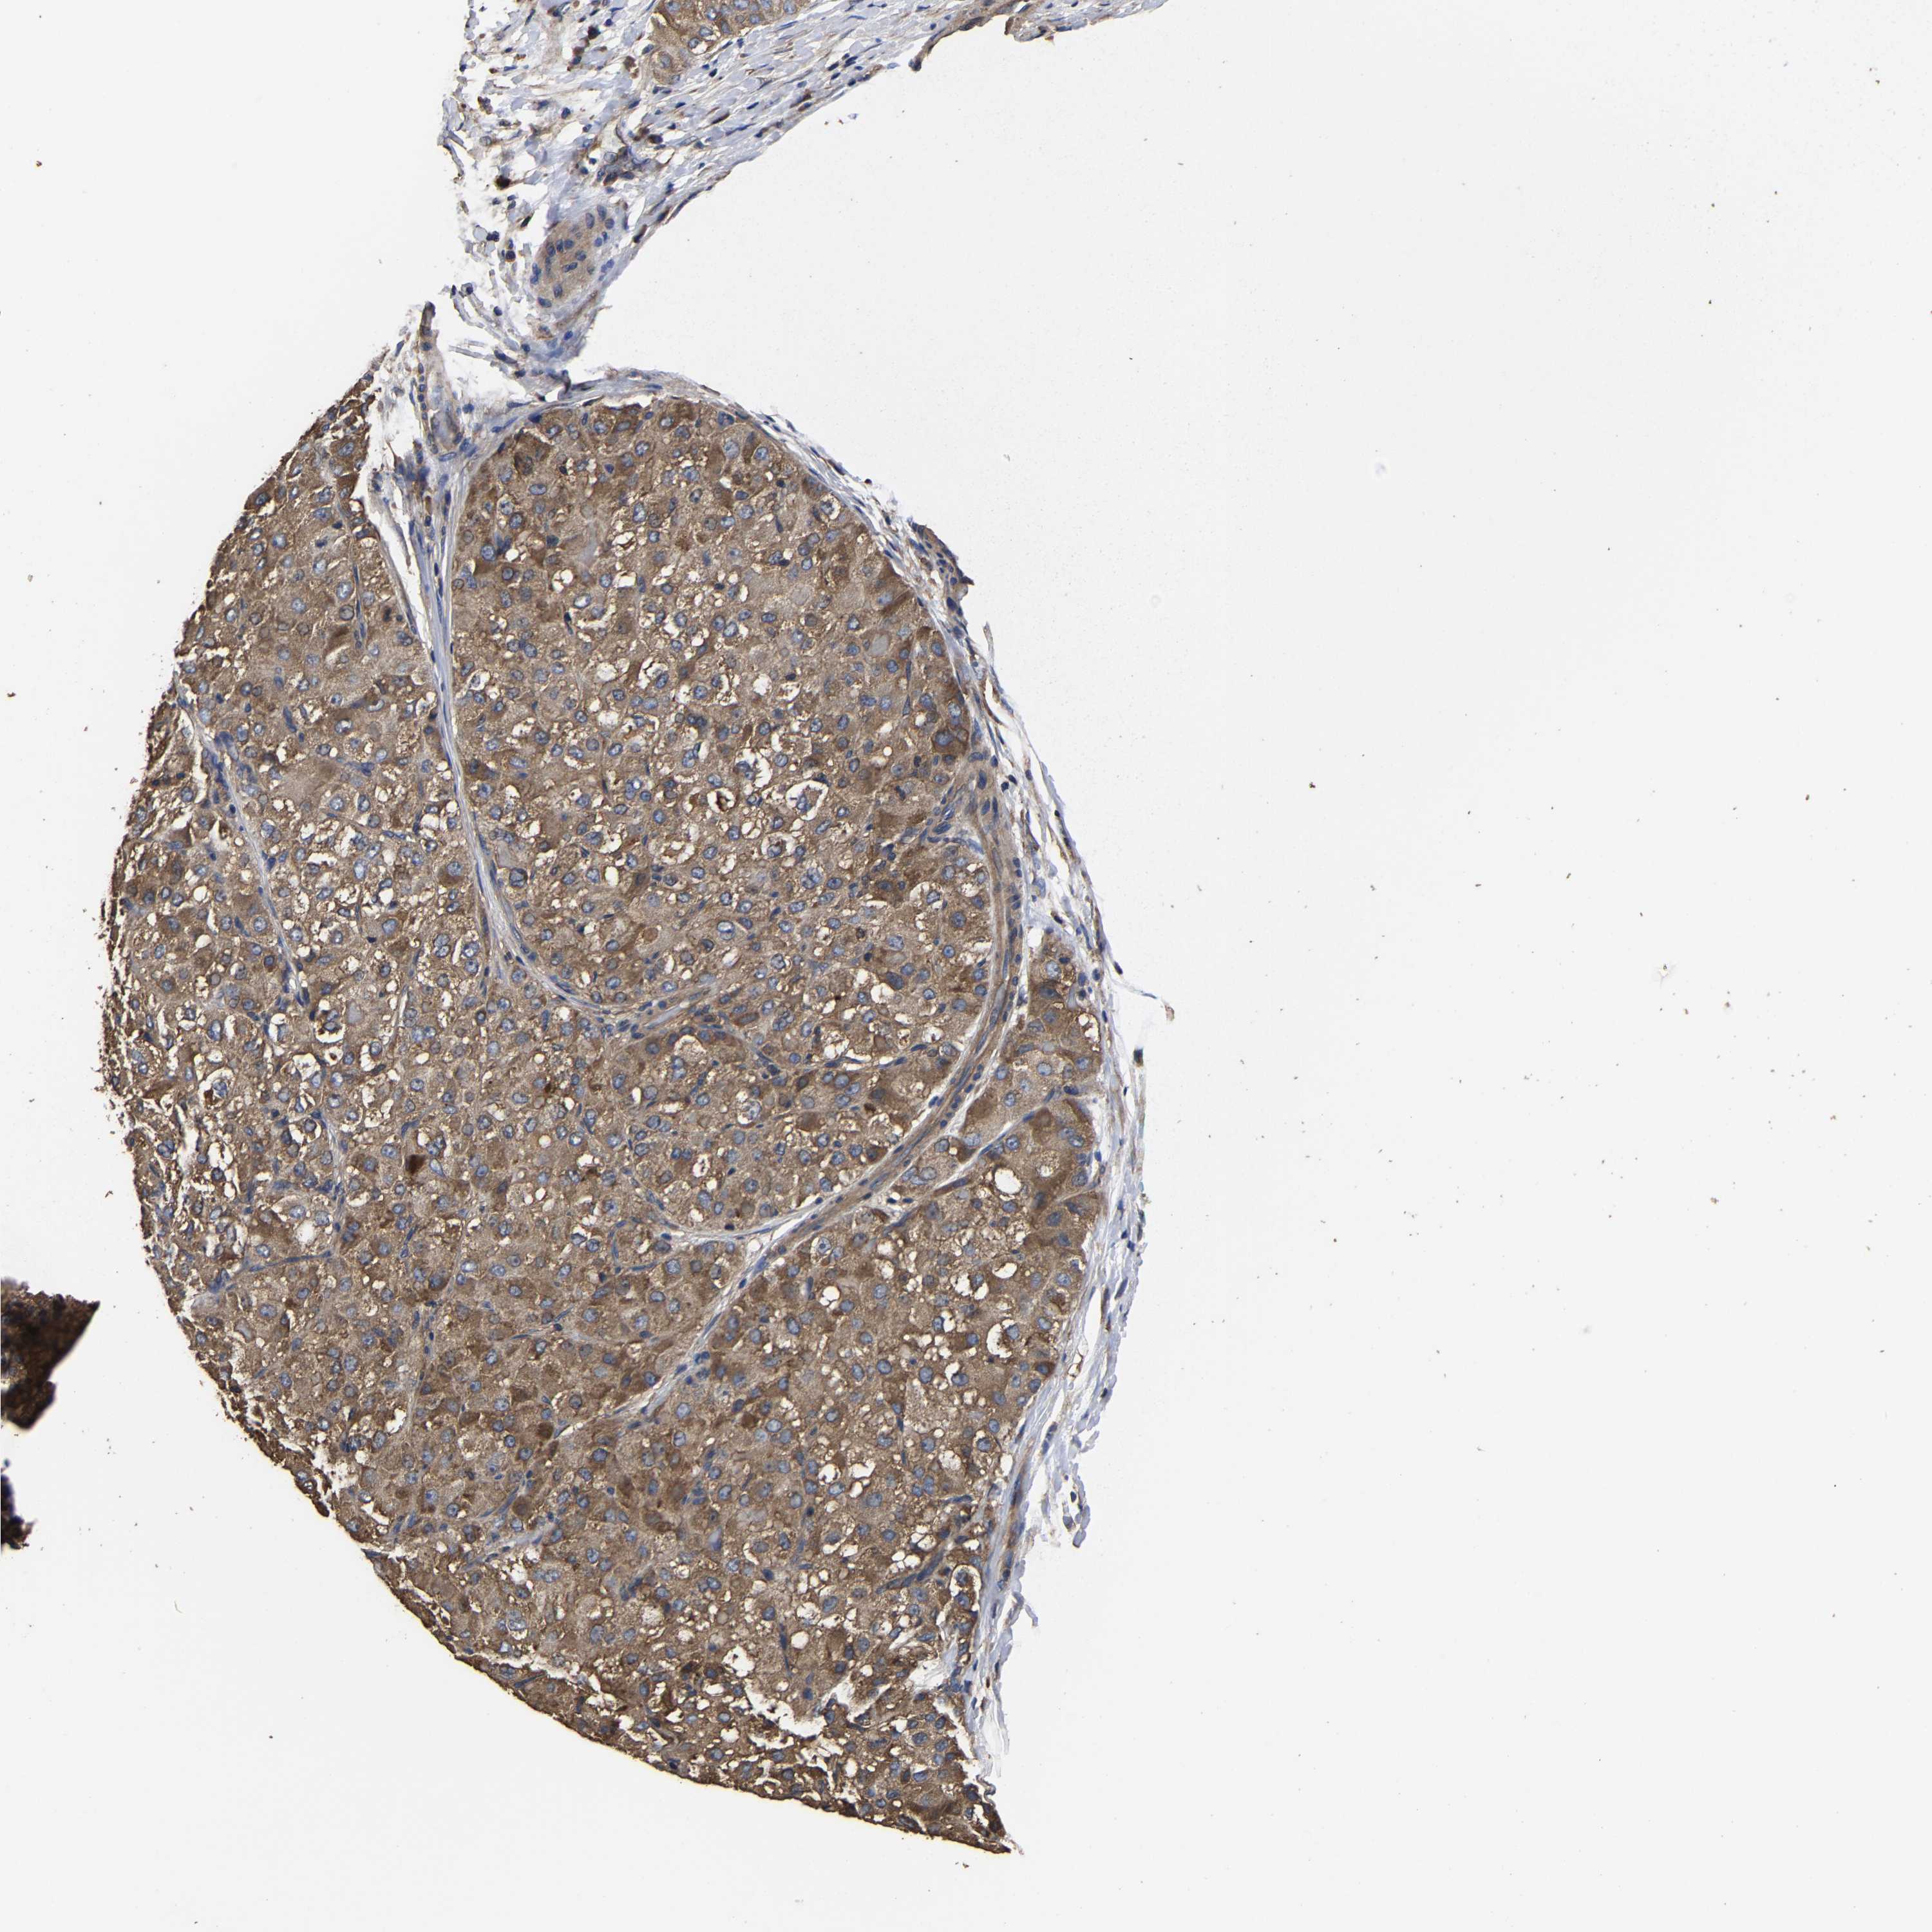

LIVER CANCER